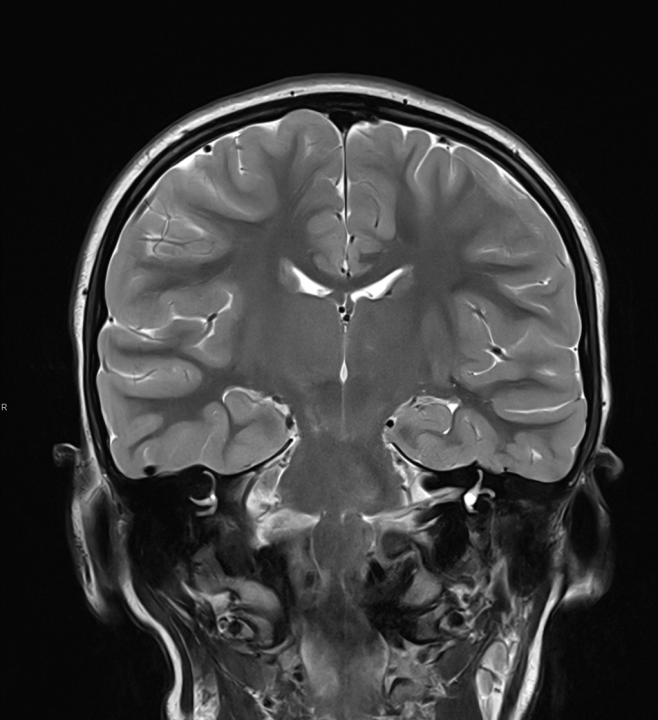

Tijekom Tjedna mozga Poliklinika Affidea Vita daje 20 posto popusta na magnetsku rezonancu!

Povodom obilježavanja Tjedna mozga od 11.